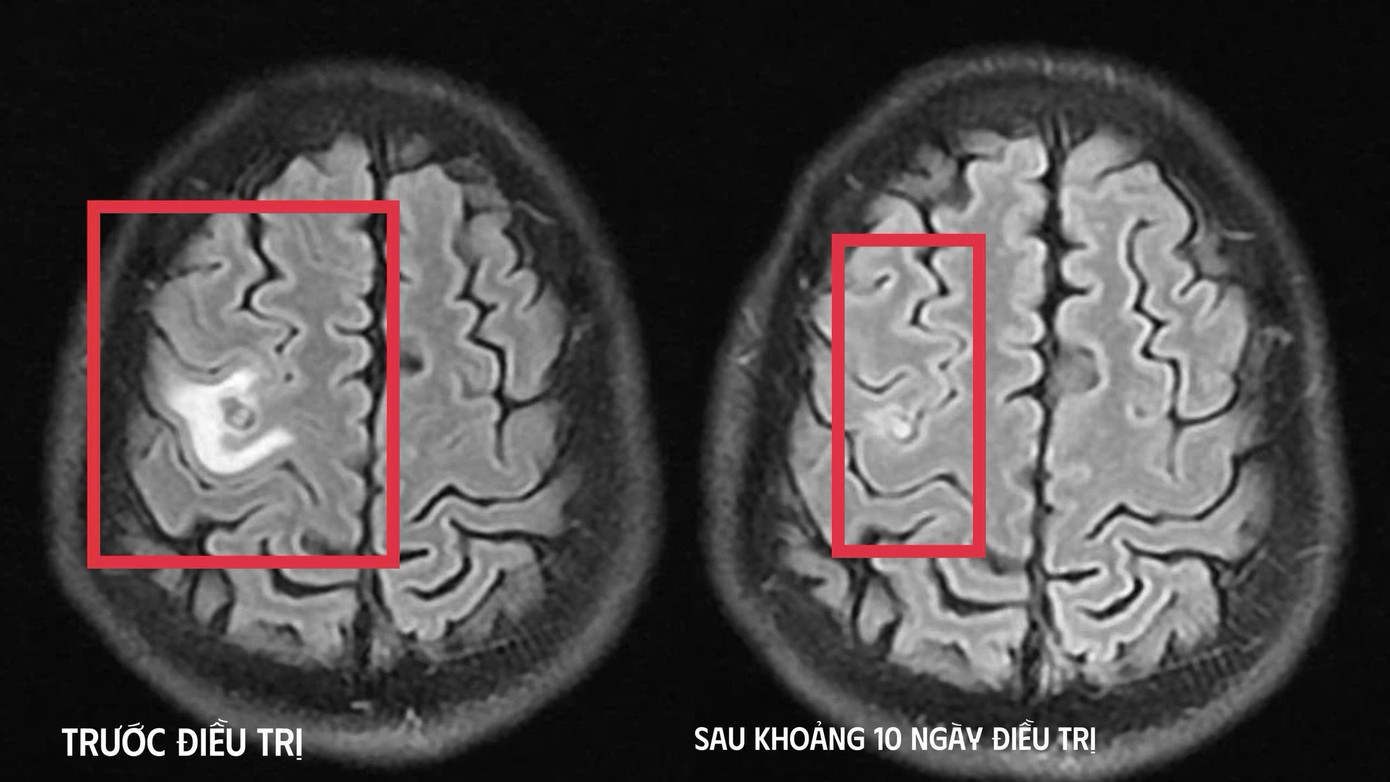

Ổ sán trước và sau điều trị trong não bệnh nhân.

Khi tái khám gần một tháng sau, kết quả chụp MRI cho thấy tổn thương não thu nhỏ rõ rệt, phù não giảm, không còn dấu hiệu tiến triển, đáp ứng điều trị tốt. Bệnh nhân được chỉ định thêm một đợt thuốc củng cố và theo dõi lâu dài.